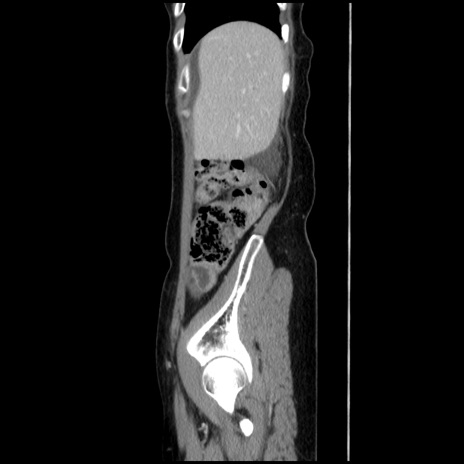

症例32(矢状断像)

【症例】40歳代 女性

【主訴】上腹部痛、嘔気・嘔吐

【現病歴】約9時間前頃から急に上腹部痛、嘔気、嘔吐が出現。改善しないため救急要請。

【既往歴】子宮頚癌(広汎子宮全摘術、放射線療法)、腸閉塞

【身体所見】腹部:平坦、軟、腸雑音亢進、上腹部を中心に腹部全体に圧痛あり。

【データ】WBC 8400、CRP 0.03